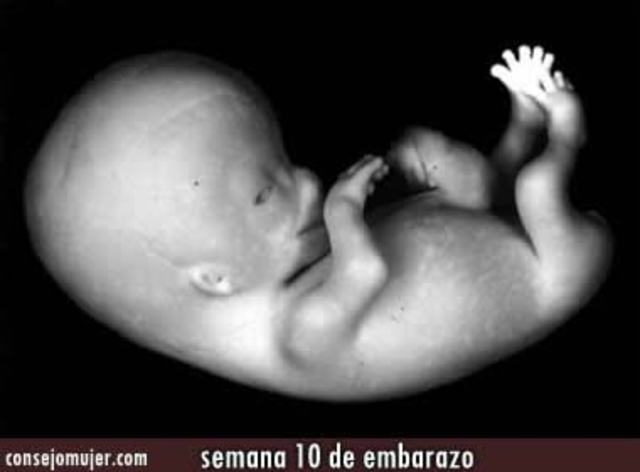

• Semana 10

Semana 10

El bebé empieza a preparase para digerir alimentos cuando nazca porque la glándula tiroidea, el páncreas y la vesícula comienzan a funcionar.

En la semana 10 de embarazo, su cerebro crece muy rápidamente más o menos a unas 250.000 nuevas neuronas por minuto.